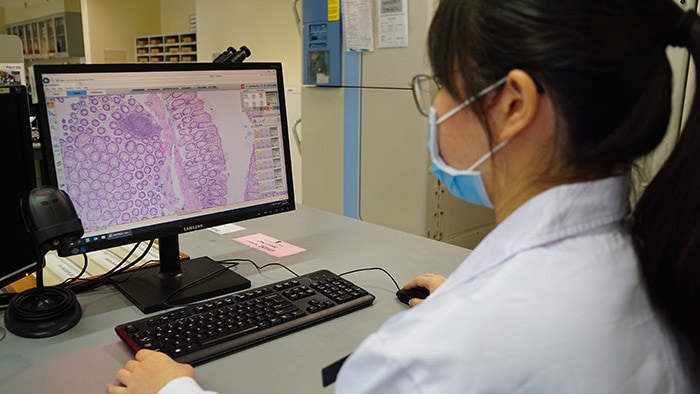

The authorization by the FDA for digital pathology in the US, the world’s largest healthcare market, constitutes a watershed moment for the healthcare industry. Pathologists work in laboratories, in clinics and on hospital wards. Digital pathology enables them to view and diagnose digital images of surgical pathology slides prepared from biopsied and resectioned tissue. It means we can leverage all the benefits that result when images are digitized, including the reporting and billing of diagnostic results.

Rather than looking directly at a tissue sample mounted on a glass slide under a conventional light microscope, the Philips IntelliSite Pathology Solution enables pathologists to read and share tissue slides digitally in order to make diagnoses. It could help make critical health information available to patients and healthcare professionals faster and at lower cost.